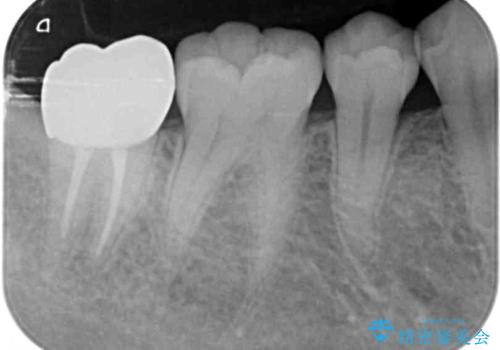

親知らずは抜去を行い、手前の第2大臼歯は根管治療後セラミッククラウンの製作を行います。

- 20万円(大臼歯根管治療・仮歯・ファイバーコア・フルジルコニアクラウン)費用は治療当時の料金となります